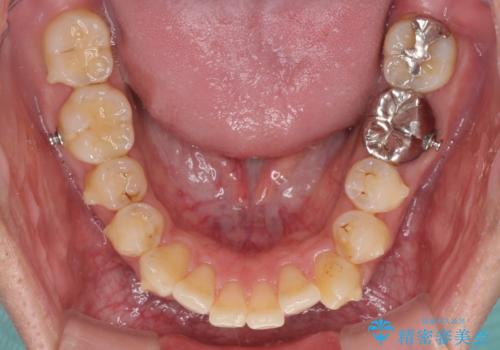

前歯のデコボコと下顎の八重歯 インビザラインによる矯正治療

- 1年4ヶ月

インビザラインを用いて、歯列を整えることとしました。

下顎前歯は後戻りを起こしやすいため、舌側を細いワイヤーで固定し、マウスピース型リテーナーで保定を行うこととしました。